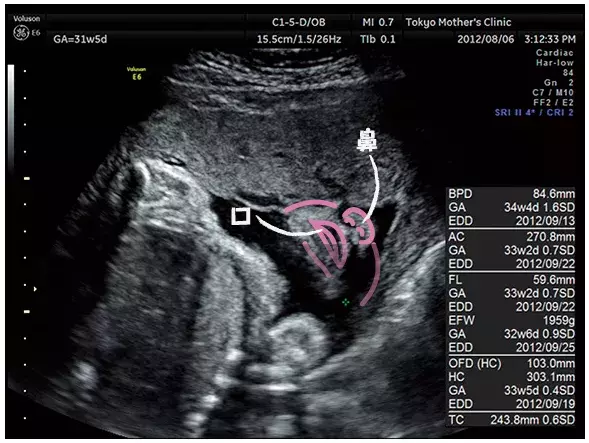

妊娠31週のエコー写真

赤ちゃんの顔を真下から見たところ。鼻の穴、口がひらいているところまで確認できる。

写真提供:東京マザーズクリニック